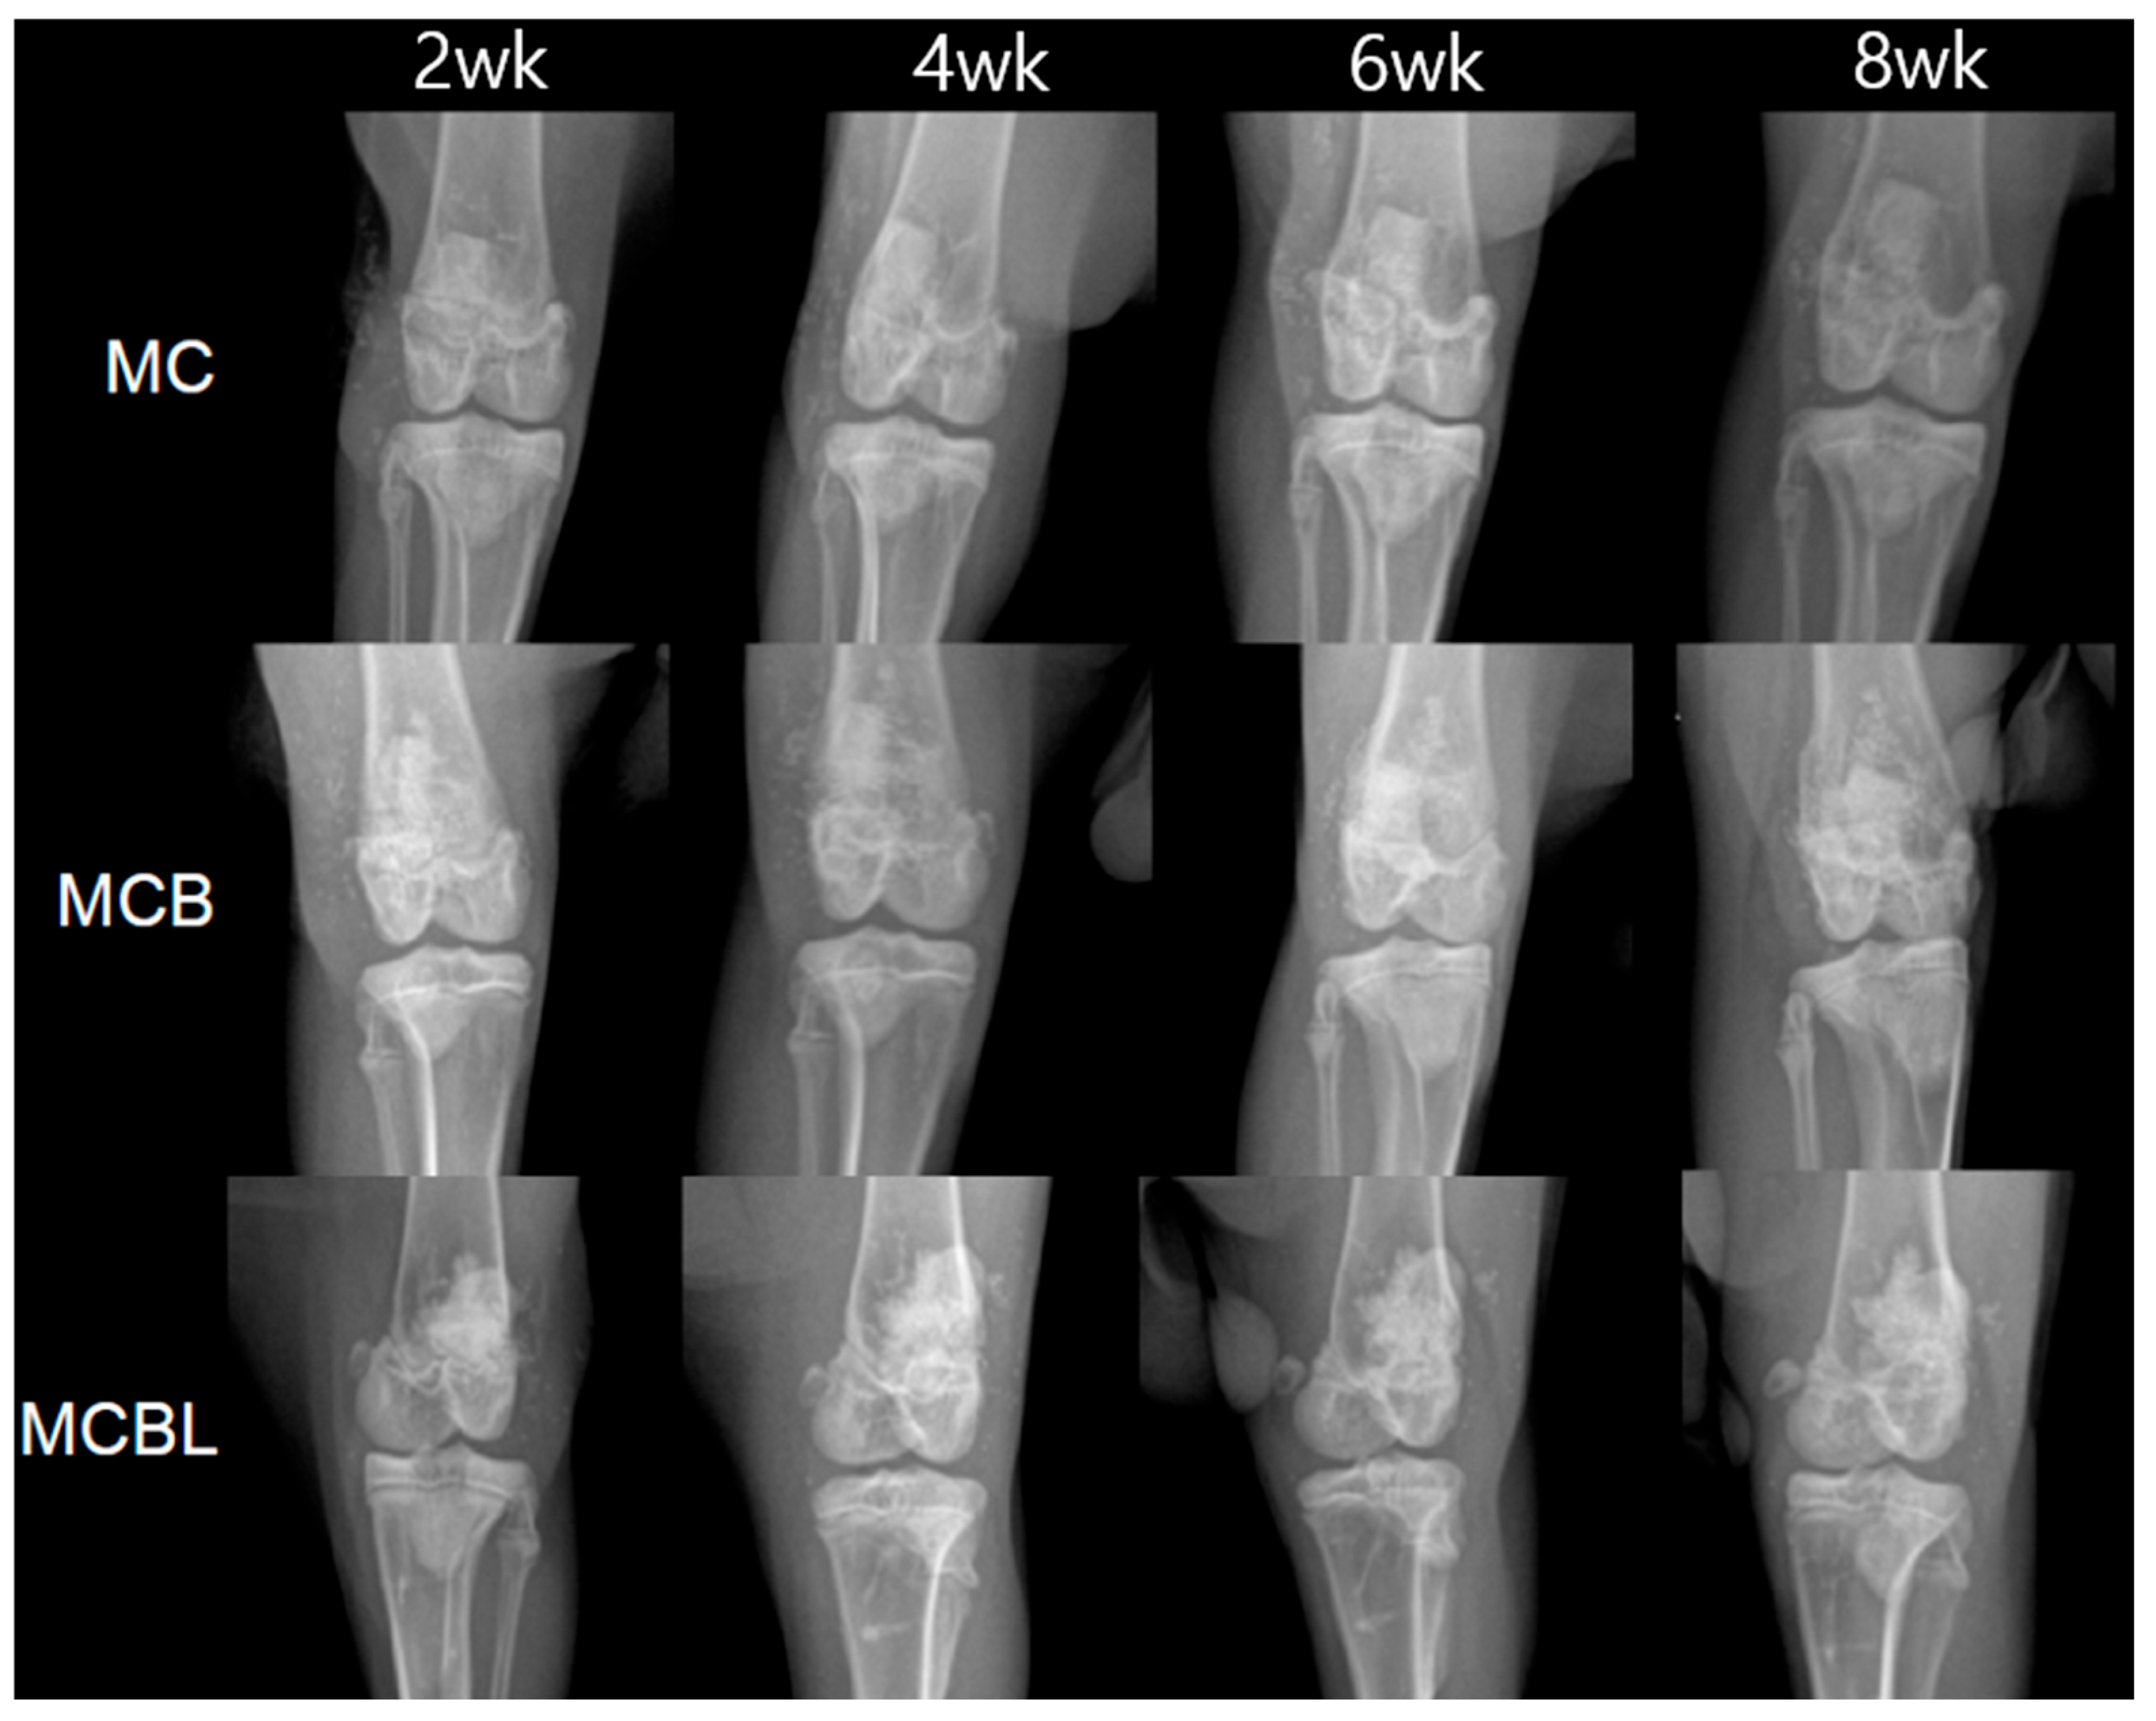

3.3.1. Radiographic Analysis of Bone Formation